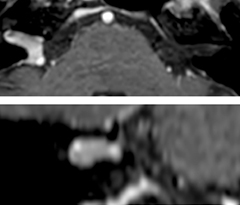

In this patient with acute right motor deficit and aphasia, the b2000 diffusion weighted image is normal. The SWIp image demonstrates more prominent veins in the right hemisphere, which could reflect increased deoxyhemoglobin contents. Fast ASL shows low CBF regions in the left frontal lobe. A follow-up ASL after one hour demonstrates high CBF values in the same area. The final diagnosis was migraine with aura.